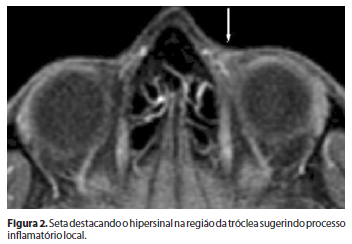

Foram solicitados exames laboratoriais (hemograma completo, fator reumatóide, fator antinuclear, anti-RO/SS-A, anti-LA/SS-B, velocidade de hemossedimentação, proteína C-reativa, uréia, creatinina, aspartatoaminotransferase, alanina transaminase, fosfatase alcalina, gama-glutamiltranspeptidase, exame qualitativo da urina, análise do líquido sinovial, radiografia das mãos, anticorpo antipeptídiocitrulinado, sorologia para hepatite B e C, ANCA C e P, antígeno HLA-B27, complemento total e componentes, urina I e PPD) para pesquisa de doenças reumatológicas e infecciosas, estando todos dentro da normalidade. O exame de ressonância nuclear magnética (RNM) de órbita demonstrou hipersinal na região da tróclea (Figura 2) sugerindo processo inflamatório local.

A síndrome de Brown inflamatória é um tipo raro de estrabismo restritivo adquirido, no qual ocorre o acometimento do tendão do músculo oblíquo inferior de provável causa reumatológica subjacente. A manobra de tentativa de elevação mecânica do bulbo ocular com o dedo resultou em normalização da dução, o que sugere o diagnóstico de síndrome de Brown adquirida, quadro este frequentemente associado a condições inflamatórias(4-5). O quadro clínico autolimitado e recidivante, associado à alteração encontrada no exame de RNM confirmou o diagnóstico.